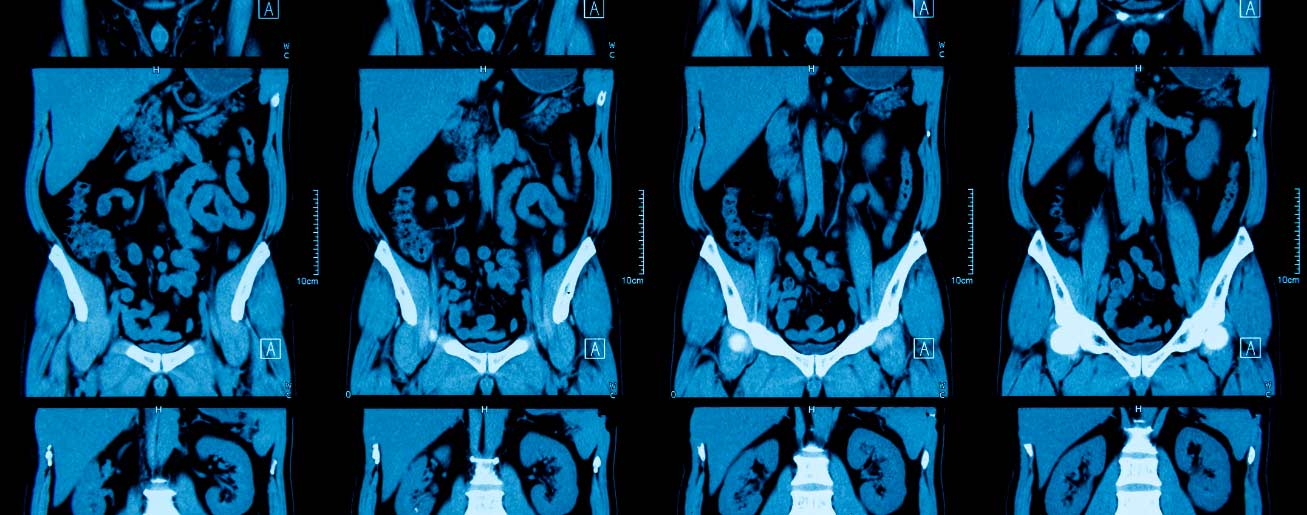

Tomografia pode Detectar Câncer? Saiba Como o Exame Ajuda

Entenda, de forma clara, se a Tomografia pode detectar câncer e como esse exame contribui para decisões médicas mais seguras e assertivas

Entenda, de forma clara, se a Tomografia pode detectar câncer e como esse exame contribui para decisões médicas mais seguras e assertivas